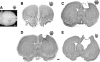

We report the results of controlled cortical impact (CCI) centered on the caudal forelimb area (CFA) of rat motor cortex to determine the feasibility of examining cortical plasticity in a spared cortical motor area (rostral forelimb area, RFA). We compared the effects of three CCI parameter sets (groups CCI-1, CCI-2, and CCI-3) that differed in impactor surface shape, size, and location, on behavioral recovery and RFA structural and functional integrity. Forelimb deficits in the limb contralateral to the injury were evident in all three CCI groups assessed by skilled reach and footfault tasks that persisted throughout the 35-day post-CCI assessment period. Nissl-stained coronal sections revealed that the RFA was structurally intact. Intracortical microstimulation experiments conducted at 7 weeks post-CCI demonstrated that RFA was functionally viable. However, the size of the forelimb representation decreased significantly in CCI-1 compared to the control group. Subdivided into component movement categories, there was a significant group effect for proximal forelimb movements. The RFA area reduction and reorganization are discussed in relation to possible diaschisis, and to compensatory functional behavior, respectively. Also, an inverse correlation between the anterior extent of the lesion and the size of the RFA was identified and is discussed in relation to corticocortical connectivity. The results suggest that CCI can be applied to rat CFA while sparing RFA. This CCI model can contribute to our understanding of neural plasticity in premotor cortex as a substrate for functional motor recovery.